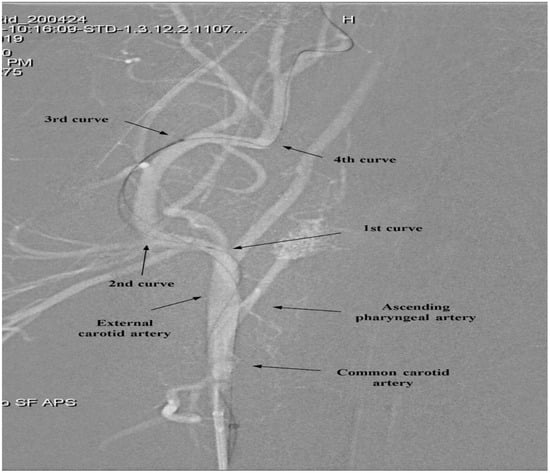

To indirectly assess the trackability and pushability of the catheters in vivo, two parameters were analyzed: (1) the catheter tension angle (CTA) and (2) the pass of catheter (POC) through the final ECA curvature. The CTA was defined as the angle formed between a vertical reference line projected from the center of the horizontal parent artery and the distal shaft of the catheter, serving as an indicator of trackability. As both catheters successfully traversed the 1st, 2nd, and 3rd curves, measurements of CTA were taken between the 3rd and 4th curvatures, and POC was evaluated at the 4th curve. A larger CTA indicated greater catheter conformity and trackability within the vascular lumen. POC was defined as successful advancement of the catheter tip past the 4th curve with minimal resistance, whereas a non-pass referred to the catheter’s failure to proceed beyond this anatomical point despite applied force.

Figure 3 illustrates the segmentation of the ECA into four curves (1st–4th), which served as reference points for evaluating catheter navigation. Table 1(B) and Figure 4 present the comparative in vivo evaluation of modified and conventional coronary IV-OCT catheters, using CTA and POC through the fourth curvature of the ECA as indirect metrics of trackability and pushability, respectively.

Figure 3. Segmentation of the external carotid artery (ECA) curvature for catheter evaluation.